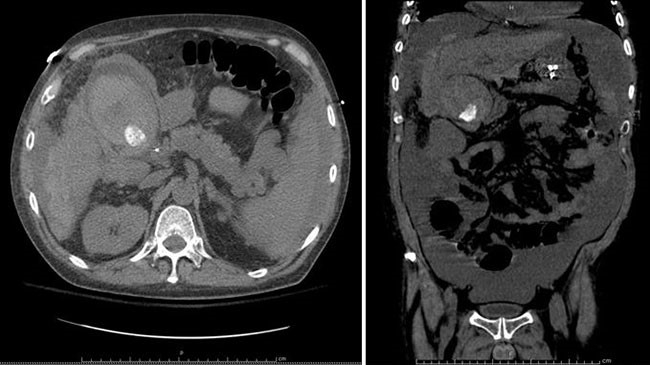

A 52-year-old male with CTP class C cirrhosis and MELD score of 40 secondary to hepatitis C virus and alcohol abuse was admitted to the hospital for hepatic encephalopathy. Additional complications of his liver disease included hydrothorax, refractory ascites, portal hypertension, and severe coagulopathy. He was admitted to the intensive care unit for management of fluid overload, pulmonary hypertension, and urgent evaluation for potential liver transplantation. Eight days following admission, the patient experienced rapid-onset abdominal pain, and the hemoglobin level abruptly decreased from 9.1 g/dL to 5.1 g/dL. A CT scan of the abdomen revealed distension of the gallbladder with intraluminal blood, as well as hemorrhage surrounding the gallbladder, sub-hepatic space, stomach, and right paracolic gutter (Figure 1). Profound hemodynamic instability ensued, leading to the decision to perform an operative exploration for presumed perforation of the gallbladder with bleeding from the wall or from adjacent varices.

Figure 1. CT of abdomen and pelvis demonstrating gallbladder distension, cholelithiasis, and intraluminal hemorrhage; blood present surrounding gallbladder, liver, stomach, and right paracolic gutter